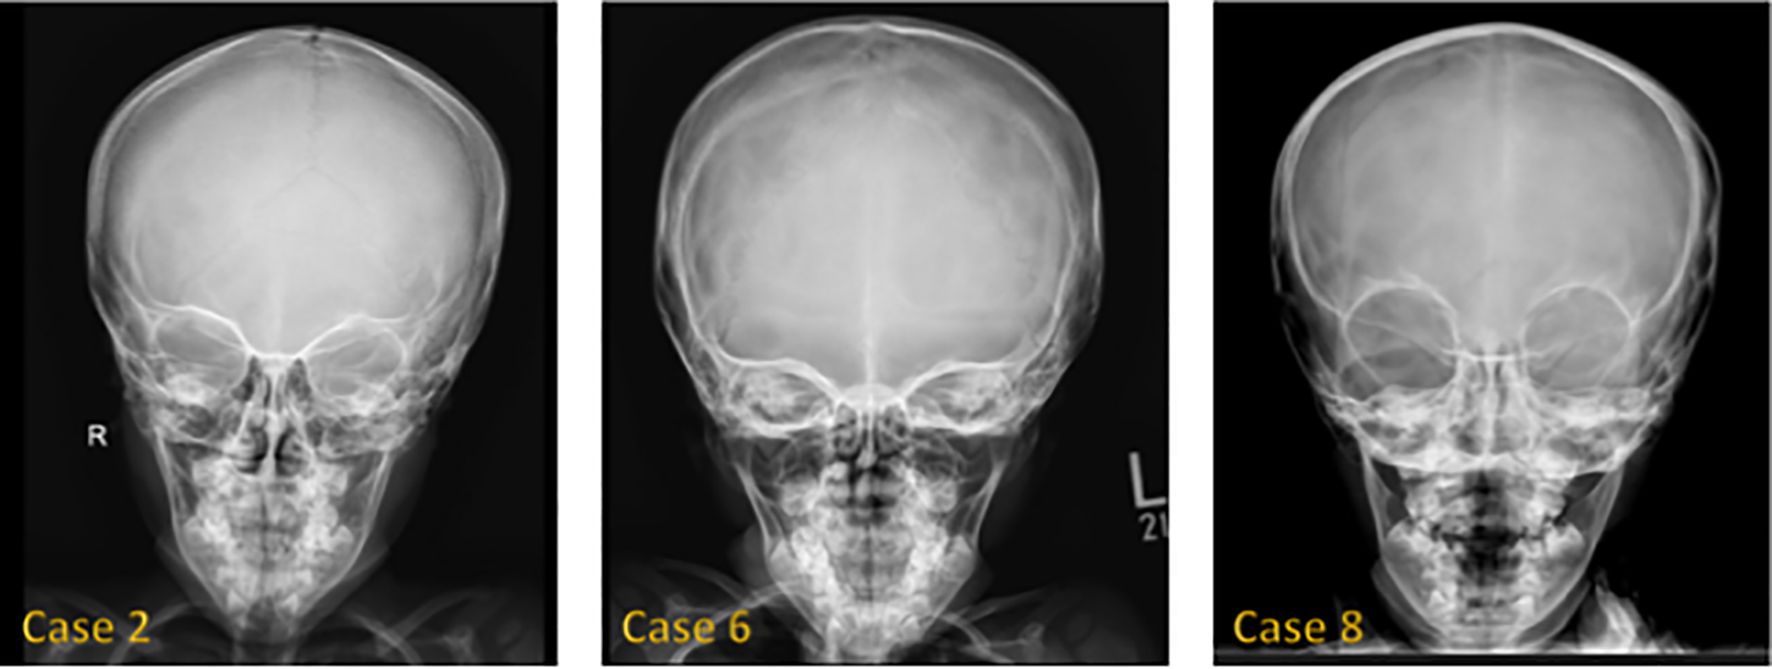

Background: 3M syndrome (3MS) is a very rare autosomal recessive disorder characterized by short stature, distinctive facial features, and skeletal abnormalities. The condition is frequently underdiagnosed due to its nonspecific symptoms and normal neurocognitive development. Few reports exist on its clinical course and response to growth hormone (GH) therapy. Therefore, this study aims to describe the clinical features of Saudi patients with 3MS and to investigate the effects of growth hormone therapy on growth. Methods: We conducted a retrospective case series of 14 Saudi patients from 11 families with genetically confirmed 3MS at King Faisal Specialist Hospital and Research Centre in Riyadh. Results: The mean age at diagnosis was 5.4 years. Consanguinity was present in 79% of cases. The most frequently affected gene was CUL7 (57% of cases), followed by OBSL1 and CCDC8. All variants were predominantly homozygous and classified as pathogenic or likely pathogenic. Clinical abnormalities included growth retardation, dental abnormalities, spinal abnormalities, and a This is a provisional file, not the final typeset article characteristic facial appearance. GH therapy was administered to 10 children; 5 demonstrated a measurable improvement in growth velocity, while 5 did not respond or discontinued treatment. IGF-1 was within/low-normal in most tested cases, with two elevated results. Conclusion: Our study highlights the extensive phenotypic variability of 3MS and underscores the predominantly autosomal recessive inheritance pattern in this population. GH therapy may provide a growth benefit in select cases, although resistance and poor response remain a challenge. Genetic testing is crucial for accurate diagnosis, individualized management, and appropriate family counseling.